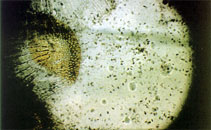

picture (UronemD0.gif) by Bassleer, G.

picture (UronemD0.jpg) by Bassleer, G.

picture (UronemD1.jpg) by Bassleer, G.

picture (UronemD2.jpg) by Bassleer, G.

picture (UronemD3.jpg) by Bassleer, G.

picture (UronemD4.jpg) by Bassleer, G.

picture (UronemD5.jpg) by Bassleer, G.

picture (UronemD6.jpg) by Bassleer, G.

picture (UronemD7.jpg) by Bassleer, G.

picture (UronemD8.jpg) by Bassleer, G.